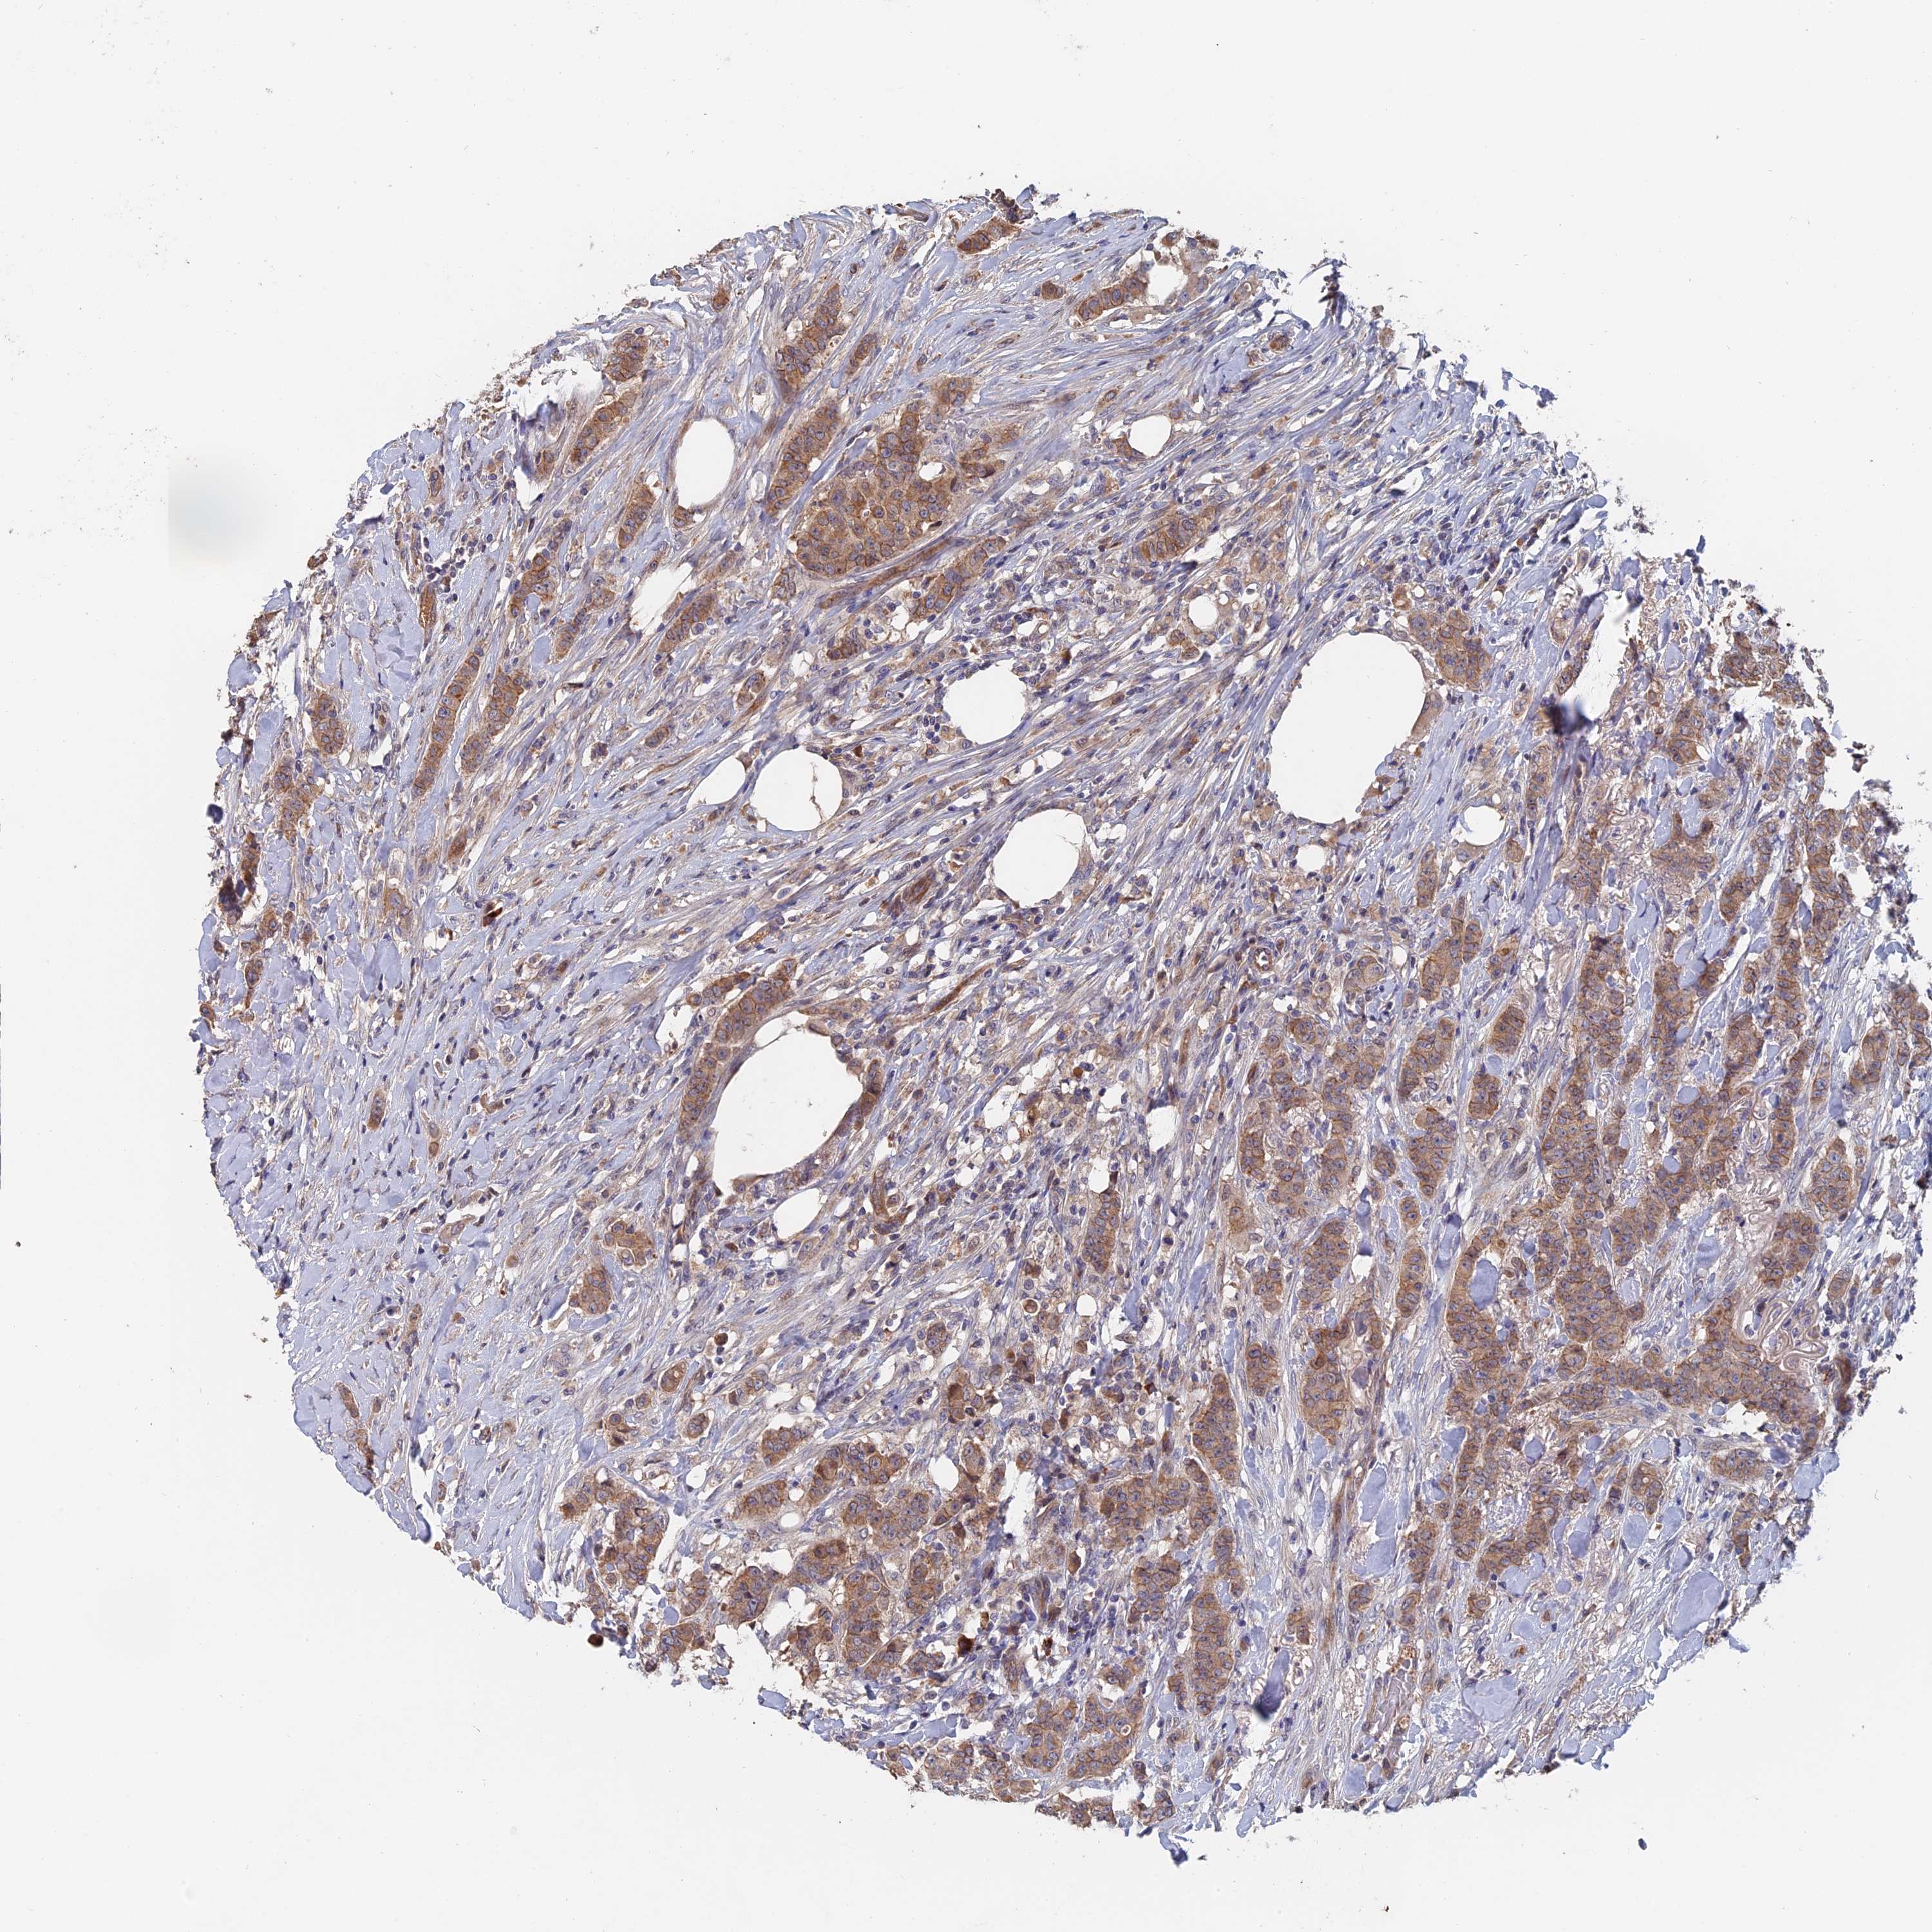

CANCER BREAST CANCER Show tissue menu

BRCA TCGA BRCA VALIDATION PROTEIN EXPRESSION